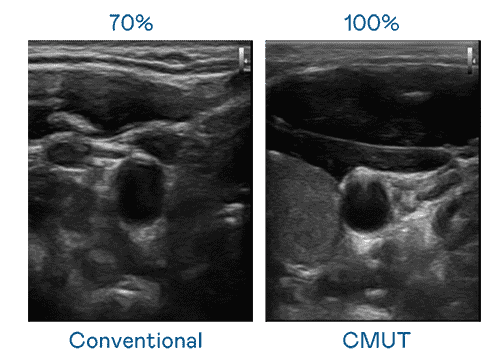

CMUT 技术是一种用电容式微机电元件来产生超音波讯号的技术。。。。与传统 PZT 压电式技术相比,,CMUT 频宽增加 30%,,,更宽频的超音波讯号让影像解析度大幅提升,,是实现高影像品质医疗超音波扫描、、、、促进精准医疗发展的关键技术。。

大频宽带来超清晰影像

超音波影像的解析度高低,,首先取决于探头能发出的讯号频宽。。。。银河集团 CMUT 可提供高清晰的超音波讯号,,,提供高频宽、、、高灵敏度、、影像纹理细节更高的超音波影像,,,,协助医护人员缩短影像判读时间及利用精准的医疗影像进行诊断。。